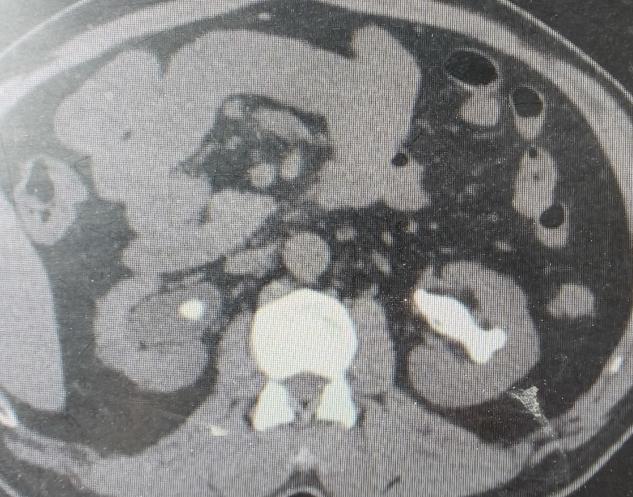

经过全面的评估和多学科会诊,泌尿外科团队为朱先生制定了周密的“两步走”微创手术方案,分期行双侧经皮肾镜取石术(同步控制血糖及治疗感染)。

· 第一步:攻坚右肾(存在积水的首先处理)。 在超声精确定位下,泌尿外科团队建立了仅铅笔粗细的微通道,利用高效的碎石设备,将右肾内坚硬的“石头城堡”逐步击碎、取出。手术顺利,手术后恢复良好。

· 第二步:清理左肾。 待右肾稳定恢复后,泌尿外科团队为左肾实施了取石手术。左侧结石更巨大、更复杂,手术团队凭借丰富的经验,再次成功完成“清剿”。

两次手术的关键,都在于 “精准穿刺” 与 “高效清石” 。既要最大程度地取尽结石,又要极其小心地保护肾功能、控制出血。整个过程,麻醉团队也为血糖的平稳控制提供了坚实保障。